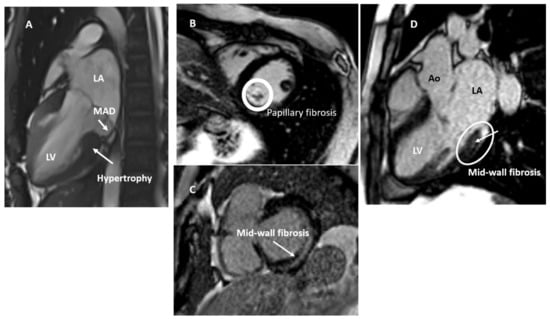

| CMR | LGE (macrofibrosis) |

| Fibrosis replacement in the basal and mid segments of the inferolateral and inferobasal wall | |

| T1 mapping (microfibrosis) | |

| Diffuse fibrosis: T1 relaxation higher than controls; T1 relaxation similar to MVP–MAD patients with positive LGE | |

| ECV increased in LGE-negative patients and can be similar to LGE-positive MVP patients | |